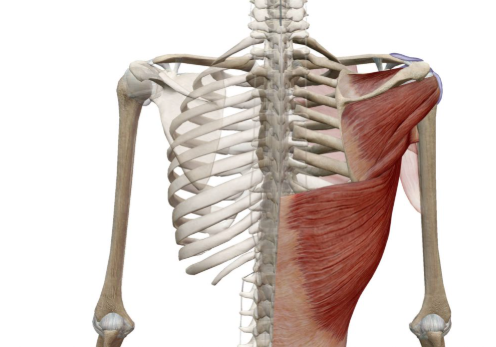

La rupture de la coiffe des rotateurs concerne un groupe de tendons et de muscles qui stabilisent et mobilisent l’épaule. En effet, une rupture, partielle ou complète, peut provoquer douleur, faiblesse et perte de mobilité. Cela survient souvent après un traumatisme ou un usage répétitif. Ainsi, il est important de consulter un spécialiste pour éviter toute aggravation.

e Dr ALLAOUI Oussama Hamza, chirurgien orthopédiste à Oran, évalue chaque cas afin de proposer le traitement le plus adapté. De plus, il peut recommander :

La rééducation et la physiothérapie pour les lésions légères.

Les exercices ciblés pour améliorer la force et la mobilité.

La réparation chirurgicale pour les ruptures importantes.

Ainsi, l’objectif est de restaurer la force, la mobilité et l’amplitude de mouvement de l’épaule. Enfin, le suivi personnalisé garantit un retour optimal aux activités quotidiennes et sportives.